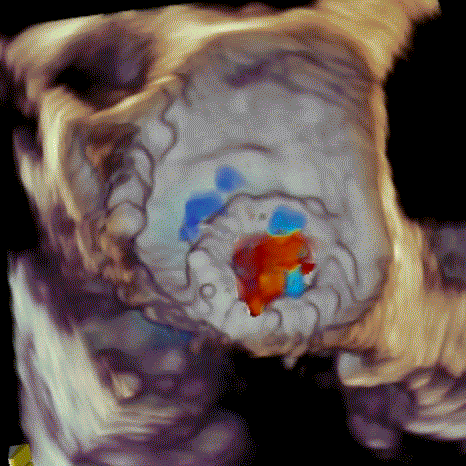

瓣中瓣植入后

无明显瓣中及瓣周反流